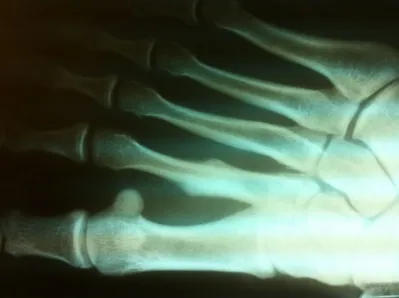

Stress fractures are relatively common to the metatarsal bones. They occur when a patient's activity level over a short period of time has been drastically increased. This can occur in a patient that starts a training season for track or any type of running the sport. It can also be seen in military recruits when they start their training season. Stress fractures of metatarsals are also common in women who change their job and all of a sudden have to wear a high-heeled shoe consistently. This puts stress on the metatarsals and causes a small fracture.

Stress fractures are often a clinical diagnosis as x-rays may be negative initially. The patient would typically experience pain and swelling across the top of the metatarsals. The pain would be mild in the morning. However, would get worse with weight-bearing. When x-rays are negative these problems are still treated as a fracture. X-rays taken 14-21 days after the injury will often show healing of the stress fracture by bone callus along the shaft of the bone.

Diaphysial stress fractures of the fifth metatarsal are more uncommon. These fractures are in an area of the fifth metatarsal bone that has a very poor blood supply. These fractures are often treated with eight weeks nonweightbearing. In rare cases, the fracture does not heal and it may require a small screw to be placed through the bone to allow the fracture to heal. In athletes that do a lot of running or those who have a foot that has a slight turning in of the front part relative to the back part of the foot, surgery may be indicated earlier due to the high propensity for refracture following healing of the primary fracture.

Stress fractures of the metatarsal are also more frequent in some patients that have long metatarsals. Treatment for these stress fractures is often just the use of a boot to unload the metatarsal during the healing process. This would be followed by an orthotic to be placed in the shoe to rebalance the weight-bearing distribution of the metatarsal heads. Long-term prognosis is usually excellent. Rarely do stress fractures fail to heal. Rarely is surgery necessary for these injuries